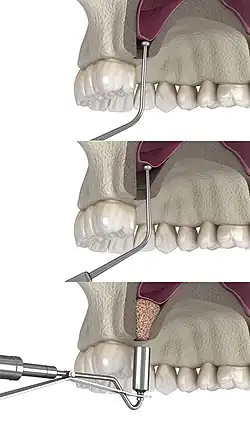

Traditional sinus augmentation or lateral window technique

The procedure is performed intraorally, where the surgeon makes an incision into the gum. Once the incision is made, the surgeon then pulls back the gum tissue, exposing the lateral bony wall of the sinus. The surgeon then creates a "window" into the sinus, exposing the Schneiderian membrane. The membrane is separated from the bone, and bone graft material is placed into the newly created space. The gums are then sutured closed, and the graft is left to heal for 4 to 12 months.[8]

The graft material can be either an autograft, allograft, xenograft, alloplast, a synthetic variant, or a combination of both.[9] Studies indicate that the lifting of the sinus membrane might result in new bone formation due to the principles of guided bone regeneration.[10] The long-term prognosis for the technique is estimated at 94%.[11]